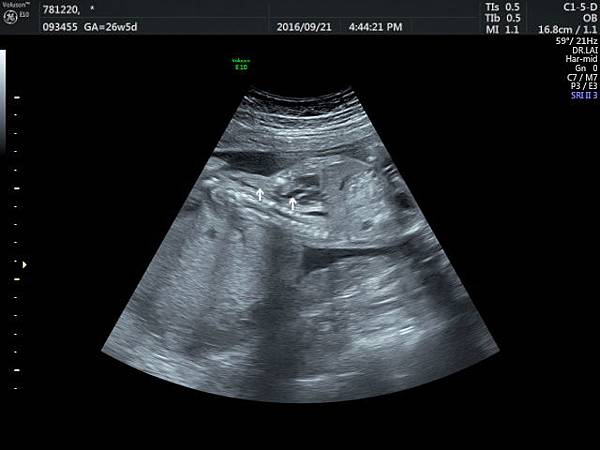

2016. 9. 21.

賴錫鉅

2016年9月21日幫一位懷孕26歲懷雙胞胎的孕婦看胎兒心臟超音波,孕婦目前26週,雙胞胎大小相差四週,高層次超音波除了小的胎兒臍動脈血流有問題之外,沒有其他異常發現,經過我的檢查,我的診斷是小的胎兒有持續性左側上腔靜脈(附圖1~5)。